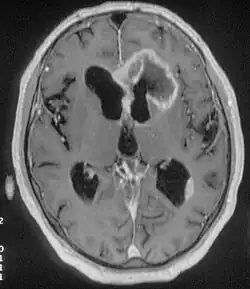

Após, dependendo dos sintomas e do exame pode ser solicitados exames como Tomografia computadorizada, com e sem contraste para tentar identificar o tumor. Ressonância Nuclear Magnética que de forma parecida com a tomografia pode dar melhor imagem do tumor, conseguindo visualizar imagens que podem não aparecer na tomografia. Tomografia por emissão de pósitrons (PET scan) é mais usado para se seguir um tratamento, distinguindo o tumor do tecido cicatricial.